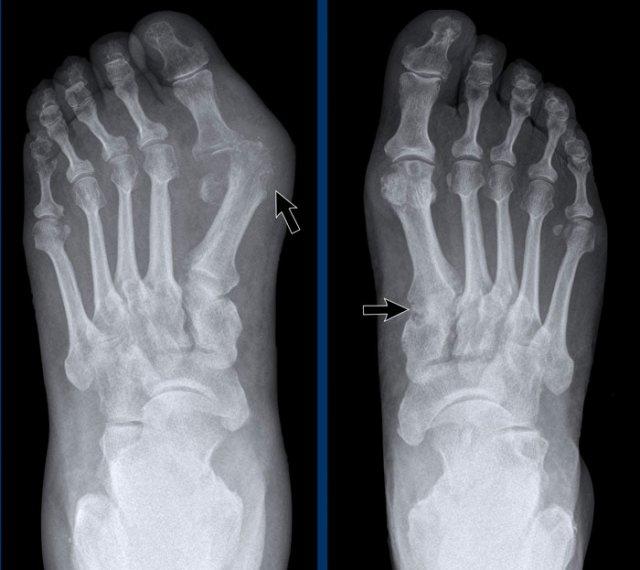

Ngón xúc xích

Hình ảnh điển hình của viêm ngón tay (dactylitis) “ngón xúc xích” với phù nề mô mềm và biến dạng bút chì trong cốc tại khớp liên đốt xa (DIP) 1-2 và 5 của bàn tay trái ở bệnh nhân viêm khớp vảy nến.

Lưu ý rằng các khớp bàn ngón tay (MCP) không bị tổn thương (khác với viêm khớp dạng thấp).

Viêm khớp vảy nến tiến triển

- Hình bên trái cho thấy bào mòn xương ở rìa khớp (mũi tên đen) và hình thành xương mờ nhạt (mũi tên xanh) tại khớp liên đốt ngón (IP).

- Về sau, bệnh tiến triển thành biến dạng bút chì trong cốc điển hình.

Phân bố tổn thương và sự hình thành xương khiến chẩn đoán viêm khớp dạng thấp ít có khả năng.

Các bào mòn xương ở rìa khớp và sự vắng mặt của tổn thương khớp liên đốt xa (DIP) ở các khớp khác khiến chẩn đoán viêm xương khớp bào mòn ít có khả năng, mặc dù biến dạng bút chì trong cốc có thể trông giống biến dạng cánh hải âu trong viêm xương khớp bào mòn.